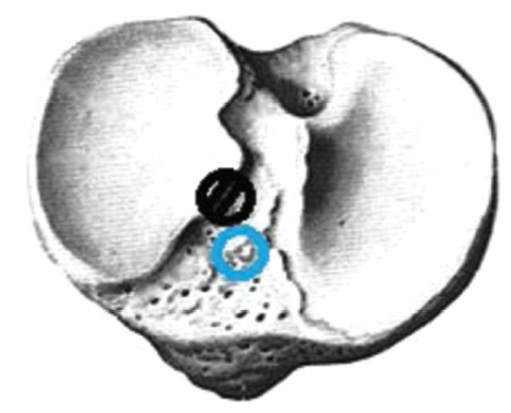

The actual revision surgery was similar to the primary ACL plastic surgery, and achieving the correct anatomical location of the channels was the focus. Since the landmarks were less clear than that in primary plastic surgery, the PCL attachment site was a landmark for the tibial channel location, and the new channel was tried to be placed in the middle and slightly medial to the intercondylar eminence. When the primary intraosseous channel was located outwardly in the tibia, we formed inwardly a new channel of a larger diameter and centered the graft in the channel using a BioIntrafix sleeve (DePuy Mitek, USA) (Fig. 1).

Fig. 1. The location of the primary tibial canal outward, — correct channel placement.

When the primary channel was displaced inwards, the graft was removed, a screw was inserted there, and a new channel with a diameter of 6–7 mm was formed. The screw was inserted to not break the wall of the new channel (Fig. 2).

Fig. 2. The location of the tibial canal inside, — correct channel placement.